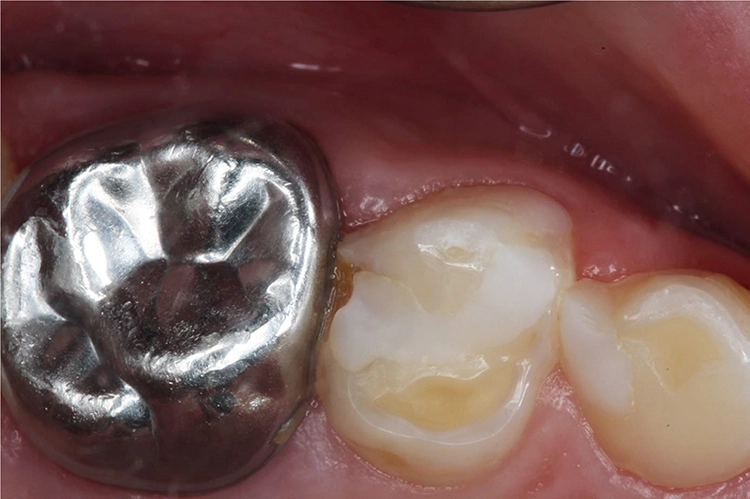

Bei einem Kontrolltermin eines 8-jährigen Jungen imponierte eine insuffiziente Füllung im linken Oberkiefer (Abb. 1). Die Anfertigung eines halbseitigen Orthopantomogramms (OPG) zeigte eine koronale Aufhellung an Zahn 64 distal (Abb. 2). Aufgrund der vollständigen mesialen Wurzel entschied man sich für den Erhalt des Zahnes 64 und eine Restauration mit einem plastischen Füllungsmaterial.

Möhn, KrämerHierfür wurde die Kavität zunächst mit einem birnenförmigen Diamanten aufgezogen und das kariöse Dentin mit einem Polymerbohrer schonend exkaviert (Abb. 3). Für die Formgebung und den Schutz des Nachbarzahnes wurde das Teilmatrizensystem Palodent® V3 verwendet (Abb. 4). Im Anschluss folgte die Füllungstherapie mittels Surefil one™ in Farbe A2.